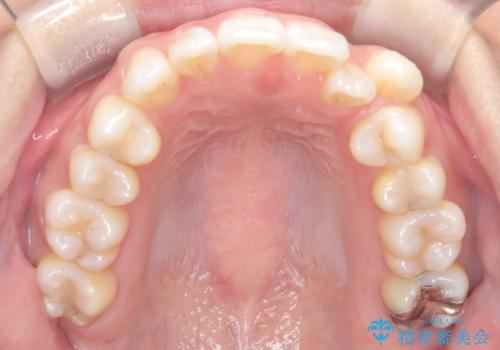

- 治療計画

上下左右の第一小臼歯を抜歯し、クリアブラケット(白い装置)とメタルワイヤーを使用して矯正を開始。初期には犬歯のアーチ内への整列を優先し、中盤からは前歯と奥歯の咬合関係の調整を進めました。審美性に優れた装置を使用したことで、治療中も目立ちにくく、見た目へのストレスが少ない点も評価されています。全体の治療は1年半で完了し、見た目・噛み合わせともに大きく改善。患者本人も「短期間でここまで変わるとは思わなかった」と満足されていました。